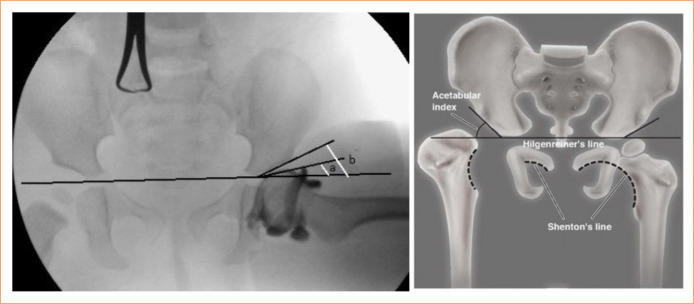

Purpose: To investigate the relationship between the cartilage acetabular index and acetabular development and secondary dysplasia.

Methods: A total of 58 hips underwent intraoperative arthrography-guided open reduction or limited open reduction due to developmental hip dysplasia between 2011 and 2015 was included in the study. We evaluated patients with acetabular angle 8º as group 2. Intraoperative acetabular cartilage index measurements were performed, and patients with low and high cartilage acetabular index were divided into two groups.

Results: There was a correlation between the cartilage acetabular index value, which indicates preoperative cartilage acetabular coverage, and acetabular development and secondary acetabular development.

Conclusion: The cartilage acetabular index is a technically easy and uncomplicated evaluation method that can be used to estimate acetabular development and should be used routinely together with the bone acetabular index.